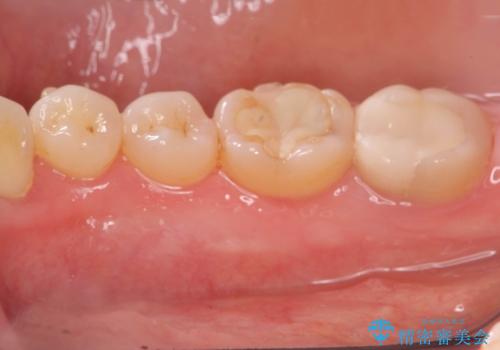

発音の邪魔となる骨隆起の除去

- 徐々に大きくなってきた骨隆起の除去を希望され来院されました。

下顎隆起を切除することで舌を収めるスペースを確保し発音のしやすさの向上を図ります。

手術は約1時間弱で終了し、術後もほとんど腫れは出ません。